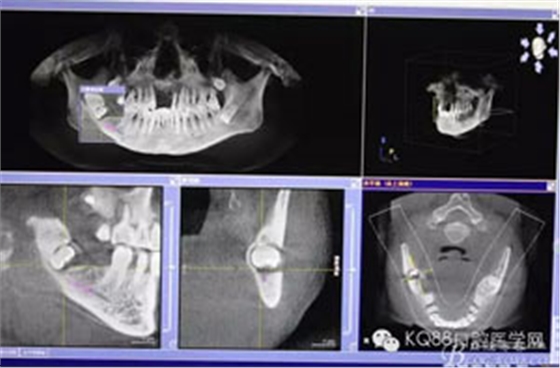

圖4.總體的CBCT影像: